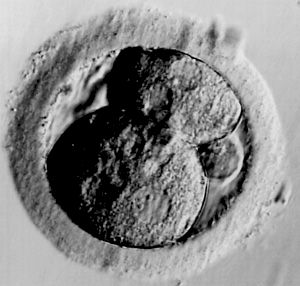

Am 19.Tag setzen sich die Keimbläschen (sog. Blastocyten) in der Gebärmutterwand fest. Diese formen embrionale Bläschen. (Ab dem 21. Tag sondern viele Hündinnen zähflüssigen, klaren Schleim ab. Das ist ein Zeichen, das der Deckakt geklappt hat)Kira geht es gut. Verändert hat sie sich kaum - sie ist schmusiger, spielt kaum mehr mit Ronja und läuft beim Walken eher lustlos nebenher. Fressen tut sie normal.

Hundeembryo

25 Tage alt

Quelle: National Geographic